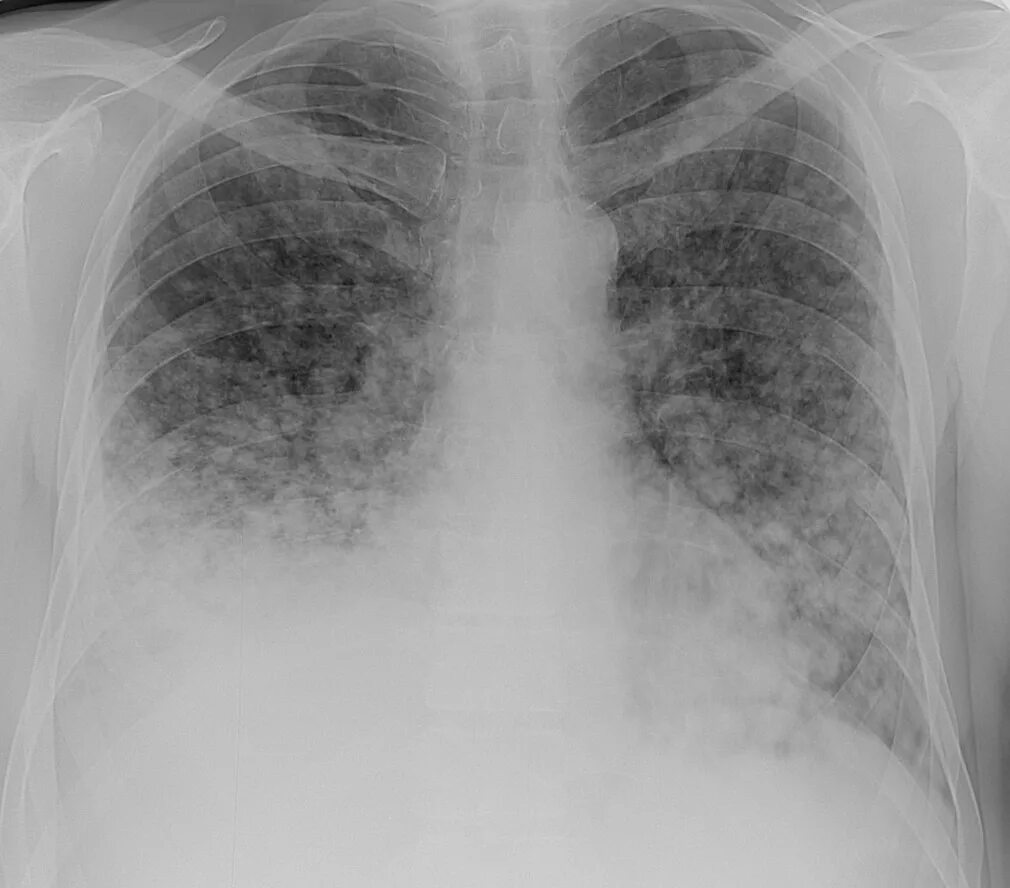

Метастазы в легких терапия